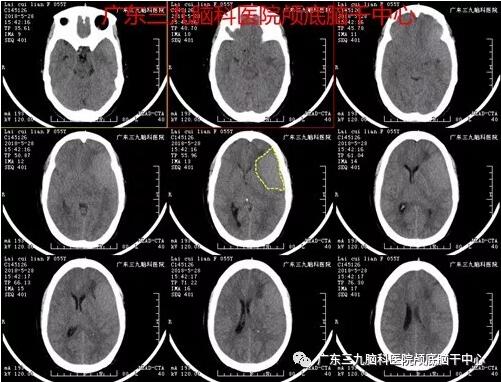

赖某,女,55岁,因头晕9天于2018年5月26日入院。影像结果示左侧额颞部大脑凸面脑膜瘤。完善相关检查后由神经外一科张良主任主刀行“左侧额颞部大脑凸面脑膜瘤切除术(语言区)”,术程顺利,术后病理报告示:脑膜皮细胞型脑膜瘤。术后语言功能保存良好。

图1:术前CT示左侧额颞顶部占位性病变,考虑脑膜瘤

图2:术前头颅CTA检查示左侧额部紧贴颅骨内板下丘样占位病变,边缘示多发来源左侧大脑中动脉M2-3段分支血管受压,部分参与供血。右侧后交通动脉起始部局限性膨大,范围约3.6mm×2.2mm,右侧胚胎型大脑后动脉。前交通动脉呈有孔型改变。